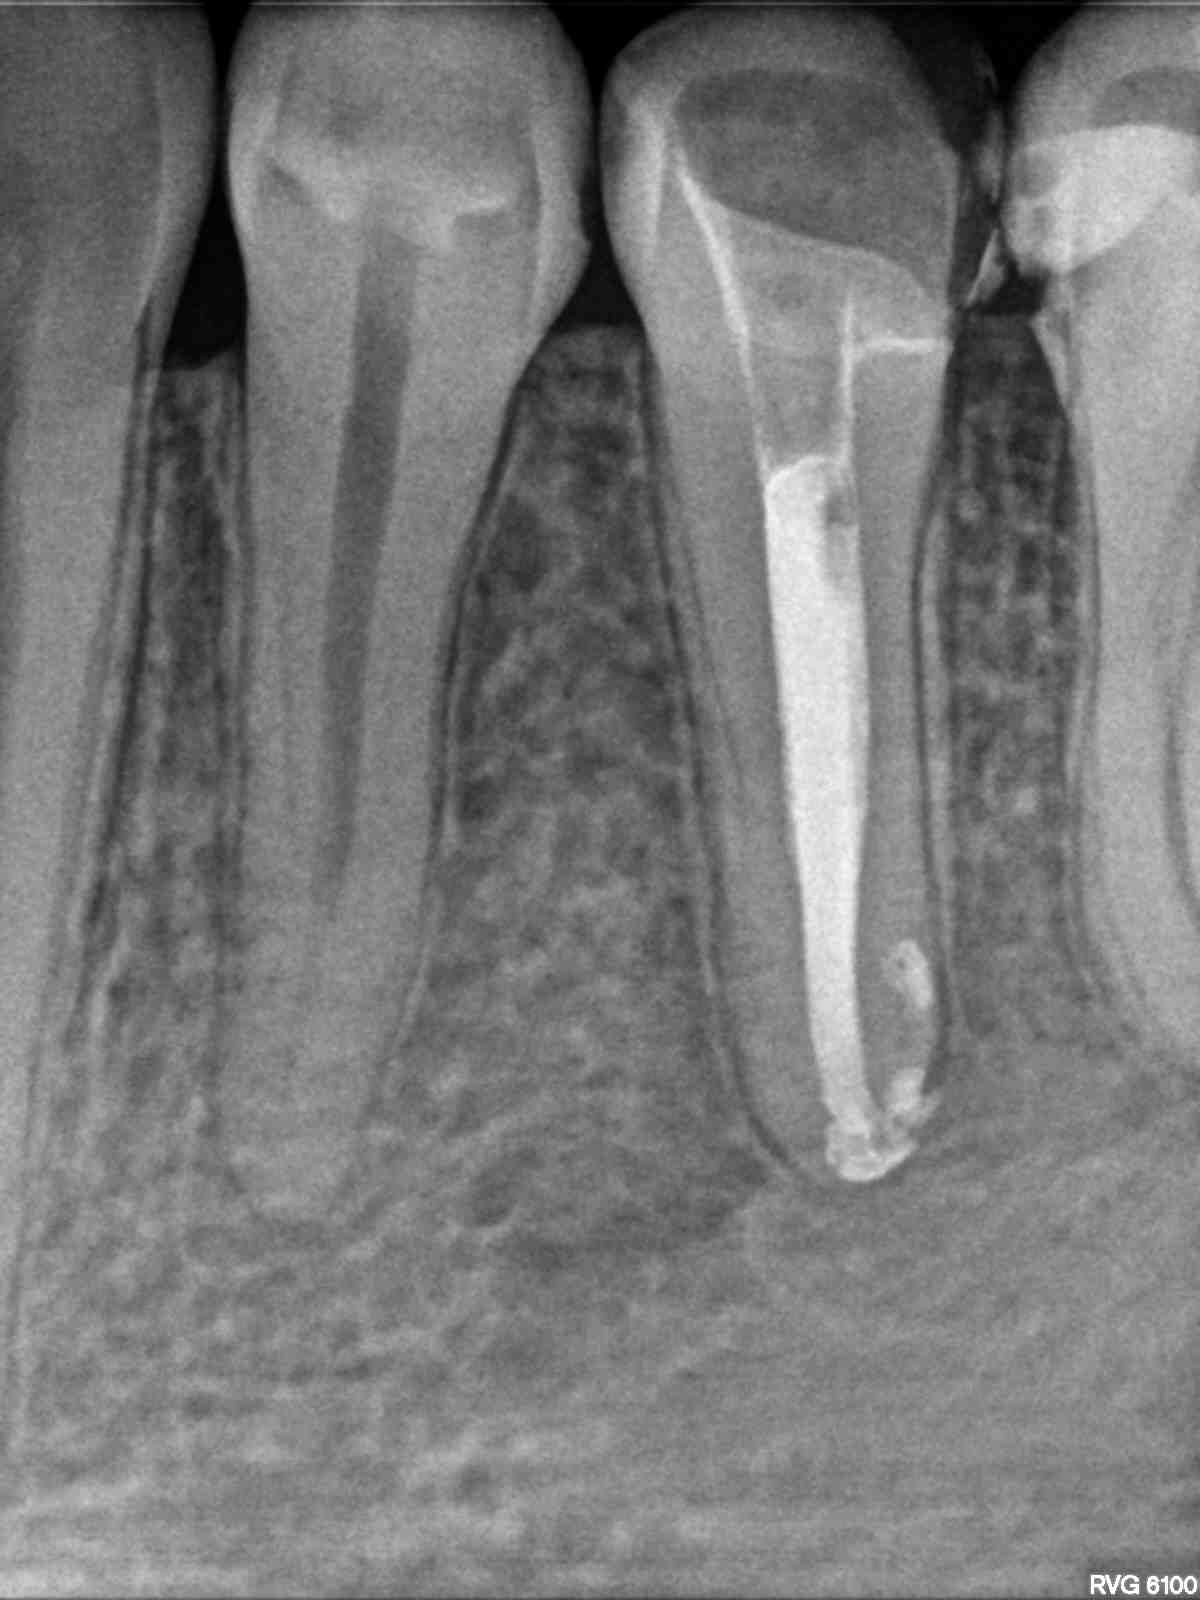

Drugi przedtrzonowiec w żuchwie uratowany. W wyniku terapii endodontycznej nastąpił całkowity zanik zmiany zapalnej w rejonie drugiego przedtrzonowca w żuchwie po lewej stronie. Leczenie kanałowe z użyciem mikroskopu była dodatkowo utrudniona ze względu na pacjenta i jego odruch refluksu. Pacjent zgłosił się do placówki NZOZ Stomatologia Bez Bólu bardzo narzekając na ból, jak określił nie do wytrzymania w żuchwie po lewej stronie. Podczas badania radiologicznego OPG i RVG stwierdzono dużą zmianę zapalną w okolicach wierzchołka korzenia drugiego przedtrzonowca w żuchwie po lewej stronie, generującą zanik kość w tym sektorze żuchwy.

Kanał wypełniono za pomocą Obtury i Systemu B ciekłą gutaperką z użyciem sealera AH+.

Stomatolog protetyk odbudował koronę zęba za pomocą Onlay’a kompozytowego.

Po 10 miesiącach na zdjęciu kontrolnym widać wyraźnie całkowite odbudowanie struktury kostnej okalającej korzeń zęba – drugiego przedtrzonowca w żuchwie po lewej stronie.